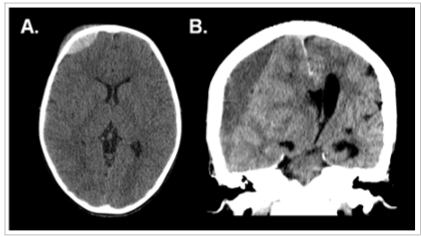

As imagens a seguir referem-se a dois pacientes diferentes, previamente hígidos, com traumatismo cranioencefálico.

Em relação às características das lesões intracranianas evidenciadas tem-se que: